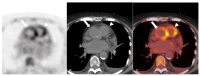

Systemic vasculitides are a rare and complex group of diseases that can affect multiple organ systems. Clinically, presentation may be vague and non-specific and as such, diagnosis and subsequent management are challenging. These entities are typically classified by the size of vessel involved, including large-vessel vasculitis (giant cell arteritis, Takayasu's arteritis, and clinically isolated aortitis), medium-vessel vasculitis (including polyarteritis nodosa and Kawasaki disease), and small-vessel vasculitis (granulomatosis with polyangiitis and eosinophilic granulomatosis with polyangiitis). There are also other systemic vasculitides that do not fit in to these categories, such as Behcet's disease, Cogan syndrome, and IgG4-related disease. Advances in medical imaging modalities have revolutionized the approach to diagnosis of these diseases. Specifically, color Doppler ultrasound, computed tomography and angiography, magnetic resonance imaging, positron emission tomography, or invasive catheterization as indicated have become fundamental in the work up of any patient with suspected systemic or localized vasculitis. This review presents the key diagnostic imaging modalities and their clinical utility in the evaluation of systemic vasculitis.